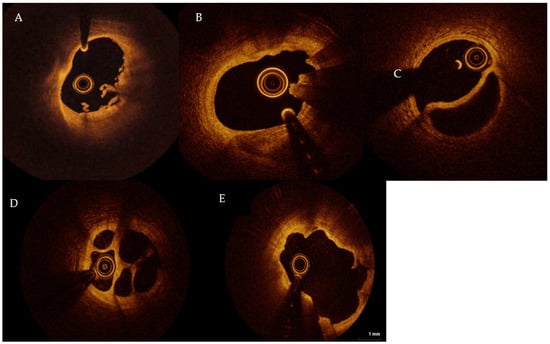

2. Role of OCT

- Jia, H.; Abtahian, F.; Aguirre, A.D.; Lee, S.; Chia, S.; Lowe, H.; Kato, K.; Yonetsu, T.; Vergallo, R.; Hu, S.; et al. In Vivo Diagnosis of Plaque Erosion and Calcified Nodule in Patients with Acute Coronary Syndrome by Intravascular Optical Coherence Tomography. J. Am. Coll. Cardiol. 2013, 62, 1748–1758. [Google Scholar] [CrossRef] [PubMed]

- Tearney, G.J.; Regar, E.; Akasaka, T.; Adriaenssens, T.; Barlis, P.; Bezerra, H.G.; Bouma, B.; Bruining, N.; Cho, J.-M.; Chowdhary, S.; et al. Consensus Standards for Acquisition, Measurement, and Reporting of Intravascular Optical Coherence Tomography Studies: A Report from the International Working Group for Intravascular Optical Coherence Tomography Standardization and Validation. J. Am. Coll. Cardiol. 2012, 59, 1058–1072. [Google Scholar] [CrossRef] [PubMed]

- Sugiyama, T.; Yamamoto, E.; Fracassi, F.; Lee, H.; Yonetsu, T.; Kakuta, T.; Soeda, T.; Saito, Y.; Yan, B.P.; Kurihara, O.; et al. Calcified Plaques in Patients with Acute Coronary Syndromes. JACC Cardiovasc. Interv. 2019, 12, 531–540. [Google Scholar] [CrossRef]

- Dai, J.; Xing, L.; Jia, H.; Zhu, Y.; Zhang, S.; Hu, S.; Lin, L.; Ma, L.; Liu, H.; Xu, M.; et al. In vivo predictors of plaque erosion in patients with ST-segment elevation myocardial infarction: A clinical, angiographical, and intravascular optical coherence tomography study. Eur. Hearth J. 2018, 39, 2077–2085. [Google Scholar] [CrossRef] [PubMed]

- Usui, E.; Matsumura, M.; Smilowitz, N.R.; Mintz, G.S.; Saw, J.; Kwong, R.Y.; Hada, M.; Mahmud, E.; Giesler, C.; Shah, B.; et al. Coronary morphological features in women with non-ST-segment elevation MINOCA and MI-CAD as assessed by optical coherence tomography. Eur. Hearth J. Open 2022, 2, oeac058. [Google Scholar] [CrossRef]

- Taruya, A.; Tanaka, A.; Nishiguchi, T.; Ozaki, Y.; Kashiwagi, M.; Yamano, T.; Matsuo, Y.; Ino, Y.; Kitabata, H.; Takemoto, K.; et al. Lesion characteristics and prognosis of acute coronary syndrome without angiographically significant coronary artery stenosis. Eur. Hearth J. Cardiovasc. Imaging 2019, 2, 202–209. [Google Scholar] [CrossRef]

- Mas-Lladó, C.; Maristany, J.; Gómez-Lara, J.; Pascual, M.; Alameda, M.D.M.; Gómez-Jaume, A.; Peral-Disdier, V. Optical Coherence Tomography for the Diagnosis of Exercise-Related Acute Cardiovascular Events and Inconclusive Coronary Angiography. J. Interv. Cardiol. 2020, 2020, 1–10. [Google Scholar] [CrossRef] [PubMed]

- Zeng, M.; Zhao, C.; Bao, X.; Liu, M.; He, L.; Xu, Y.; Meng, W.; Qin, Y.; Weng, Z.; Yi, B.; et al. Clinical Characteristics and Prognosis of MINOCA Caused by Atherosclerotic and Nonatherosclerotic Mechanisms Assessed by OCT. JACC Cardiovasc. Imaging 2022, in press. [Google Scholar] [CrossRef] [PubMed]